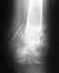

Здравствуйте! Шла, споткнулась и упала вперёд, было никак самой не встать, сделали рентген и поставили диагноз ушиб колленного сустава и частичное повреждение связок ПИС. Поставили лангет на 2 недели,после того как сняли прошло 3 дня... ногу сгибать могу в сидячем положении, в лежачем труднее, а при ходьбе опоры на ногу нет, вся опора идёт на другую ногу и колено не сгибается. Очень сильно болит икра, есть небольшая припухлость на колене. Помогите пожалуйста, когда пришла снимать лангет врач даже не посмотрел, не обследовал, поэтому очень волнуюсь вдруг что не так, раз не могу ходить.Как быть? Как лечить?